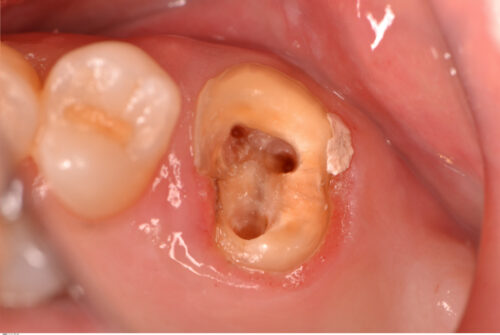

根管拡大が終わりました。ちなみに前医ではマイクロスコープを使って根管治療をしていたそうですが、患者さんのお話なので本当かどうかはわかりません。

高価な設備や機材を導入することも大切ですが、基本的な手技を堅実に行うことも大切だと思います。